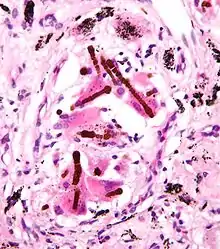

Ferruginous bodies. H&E stain.

They appear as small brown nodules in the septum of the alveolus. Ferruginous bodies are typically indicative of asbestos inhalation (when the presence of asbestos is verified they are called "asbestos bodies"). In this case they are fibers of asbestos coated with an iron-rich material derived from proteins such as ferritin and hemosiderin.[1] Ferruginous bodies are believed to be formed by macrophages that have phagocytosed and attempted to digest the fibers.

Micrograph of asbestosis with prominent ferruginous bodies. H&E stain.